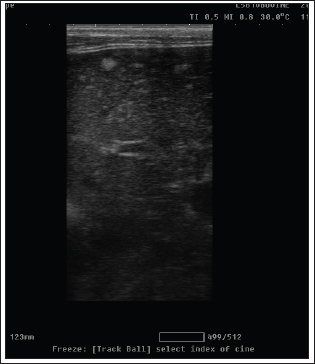

Fig. 3. Radiography images of mammary gland tissue showing enlargement of the mammary glands with intact body wall in different affected female cats. UltrasonographyOn ultrasound images, mammary gland tissue showed higher echogenicity than normal tissue. The FMH lesions were well-defined, slightly hyperechoic, lobulated masses containing multiple small anechoic clefts within the mammary parenchyma. The intraductal pattern is dominant, with anechoic areas corresponding to clefts of different shapes within the mammary gland parenchyma. The presence of clefts in mammary fibroepithelial lesions provided a more heterogeneous appearance to the ultrasound images (Fig. 4). In the solid lesions, the ultrasound pattern is more homogeneous (Fig. 5).

Fig. 5. Ultrasonographic image of a solid pattern lesion. Histopathological examinationThe microscopic appearance of feline mammary hyperplasia is described as fibroadenomatous changes with glandular and fibrous proliferation and dilated ducts. Hyperplasia of both acini (secretory units) and interlobular ducts surrounded by fibrous stroma. The mammary ducts are dilated and often filled with proteinaceous fluid or secretions (Fig. 6).